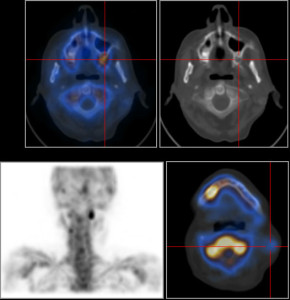

Cancro alla laringe: superato bene da 6 pazienti su 10

In Italia il 60% dei pazienti con cancro alla laringe guarisce dalla malattia. E la percentuale sale a oltre il...